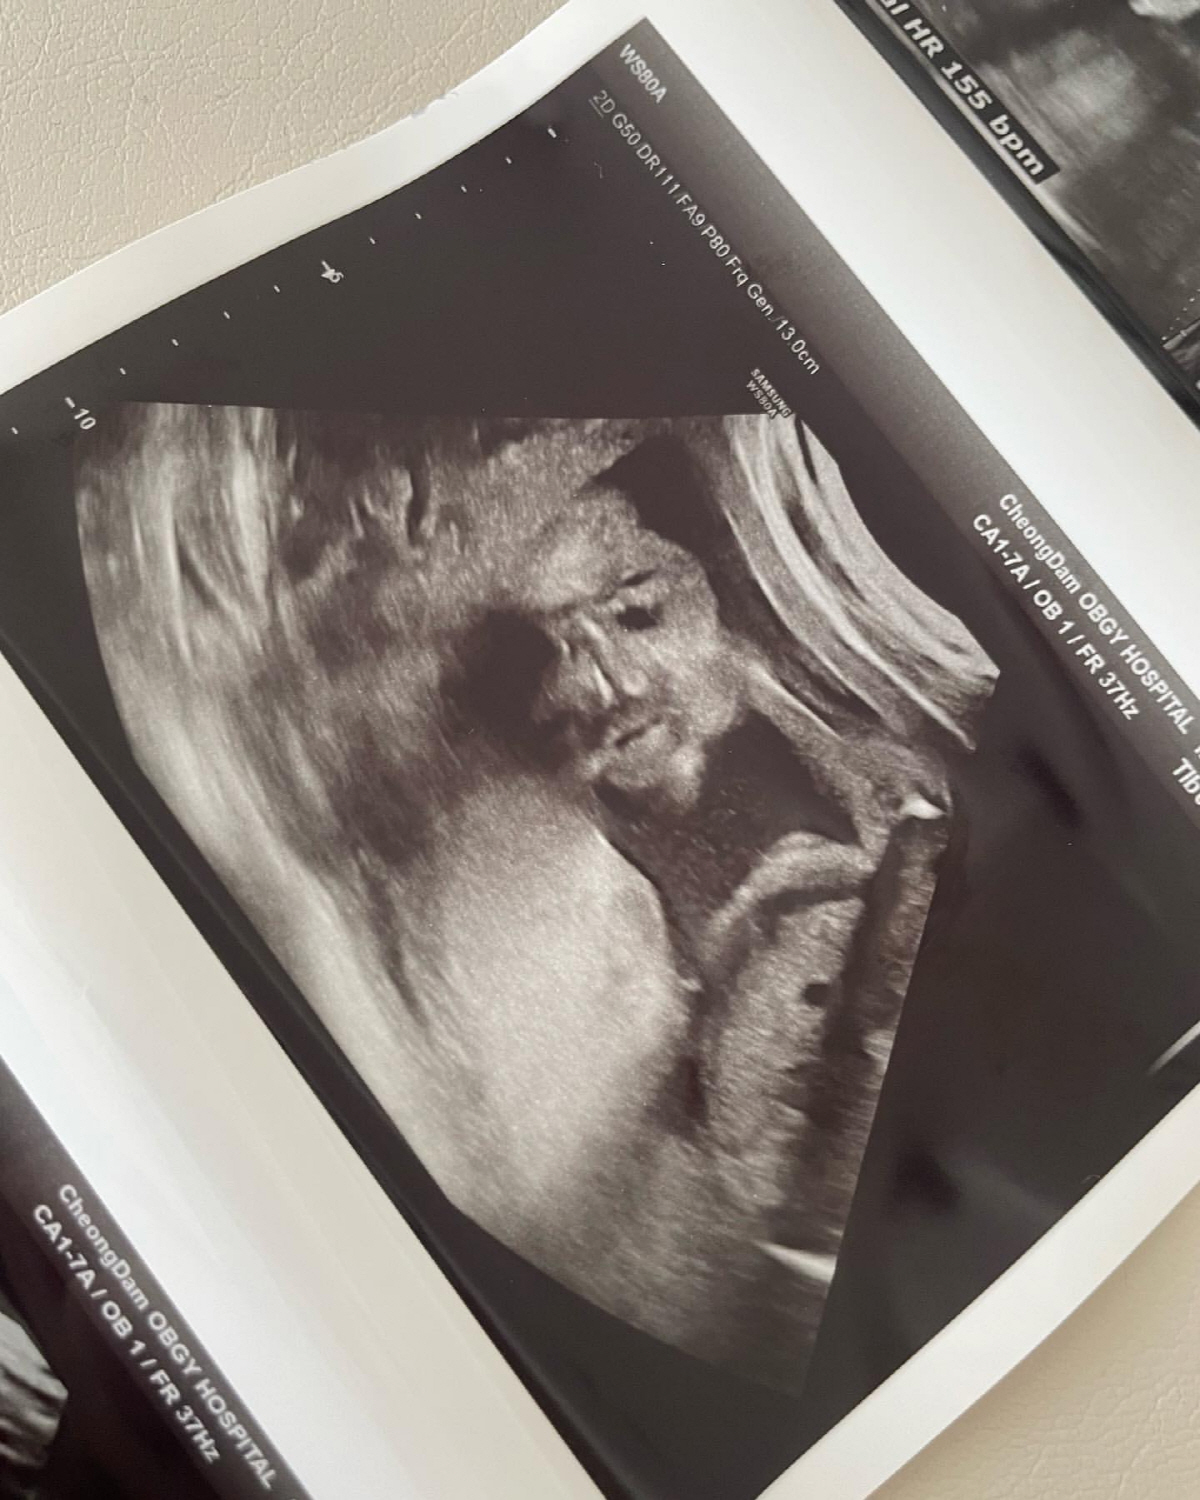

양미라는 "그래도 요즘은 서호 임신 때부터 혼자 마시던 부기차를 다시 먹기 시작했더니 뭔가 훨씬 가뿐하고 사진에도 부기가 확실히 덜해요"라고 전했다. 이어 "그나저나 썸머도 서호 때처럼 초음파 사진이 굴욕적이네요. 뭔가 교과서에서 본 듯한. 모아이 석상 같아요"라며 아기 초음파 사진을 공개했다.